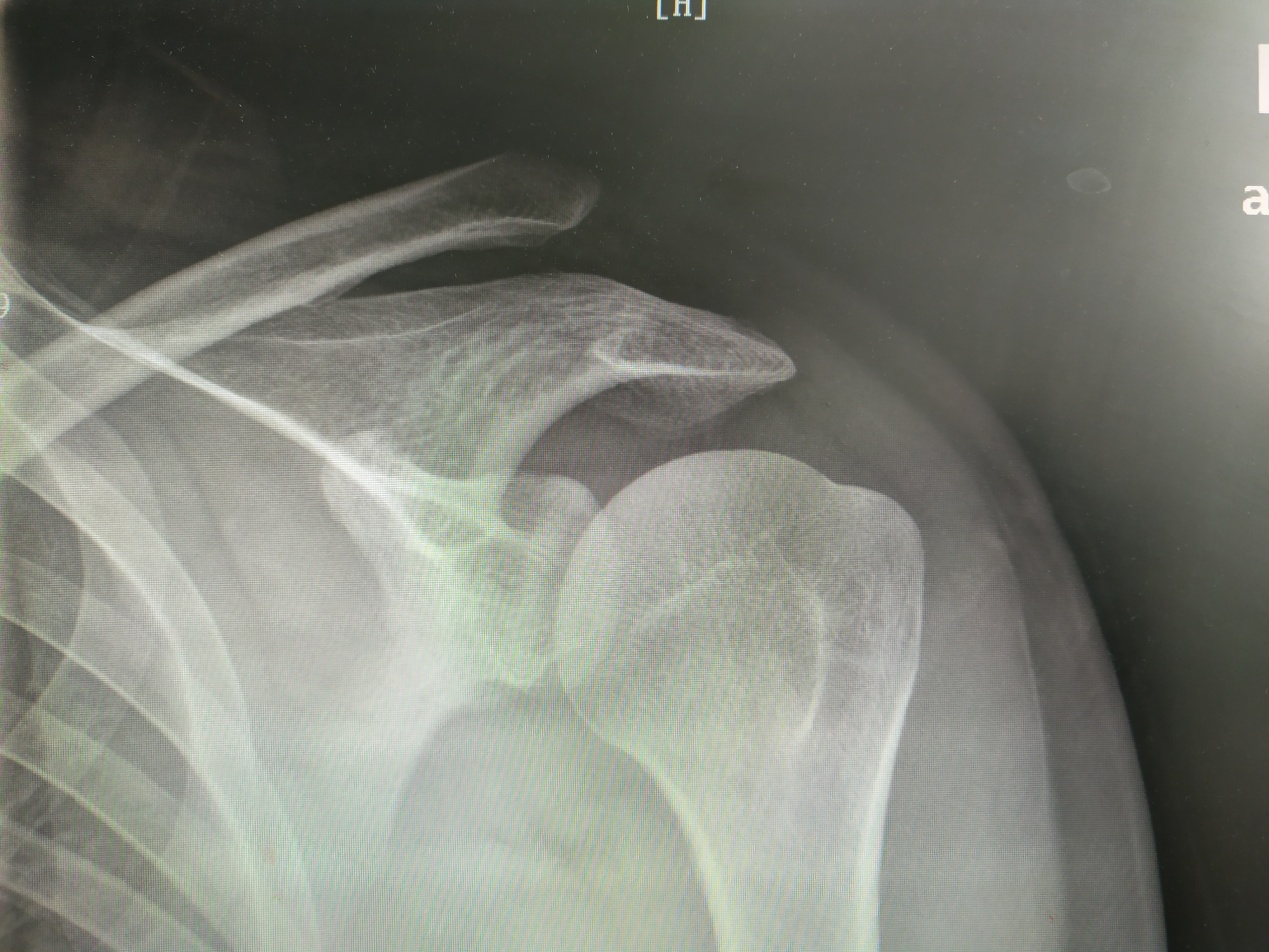

当韧带完全受损时,就会造成肩锁关节脱位,锁骨上翘。

失去限制的锁骨受颈部肌肉的牵拉而上移,导致其远端突出于皮肤表面,虽然这不是骨折,但也会伴有剧烈的疼痛,严重影响上肢的运动,武磊的这一体征就很典型,虽然他这应该是陈旧伤。

从分型上他应该属于TossyIII型,就是两组韧带都断了,是需要手术的。